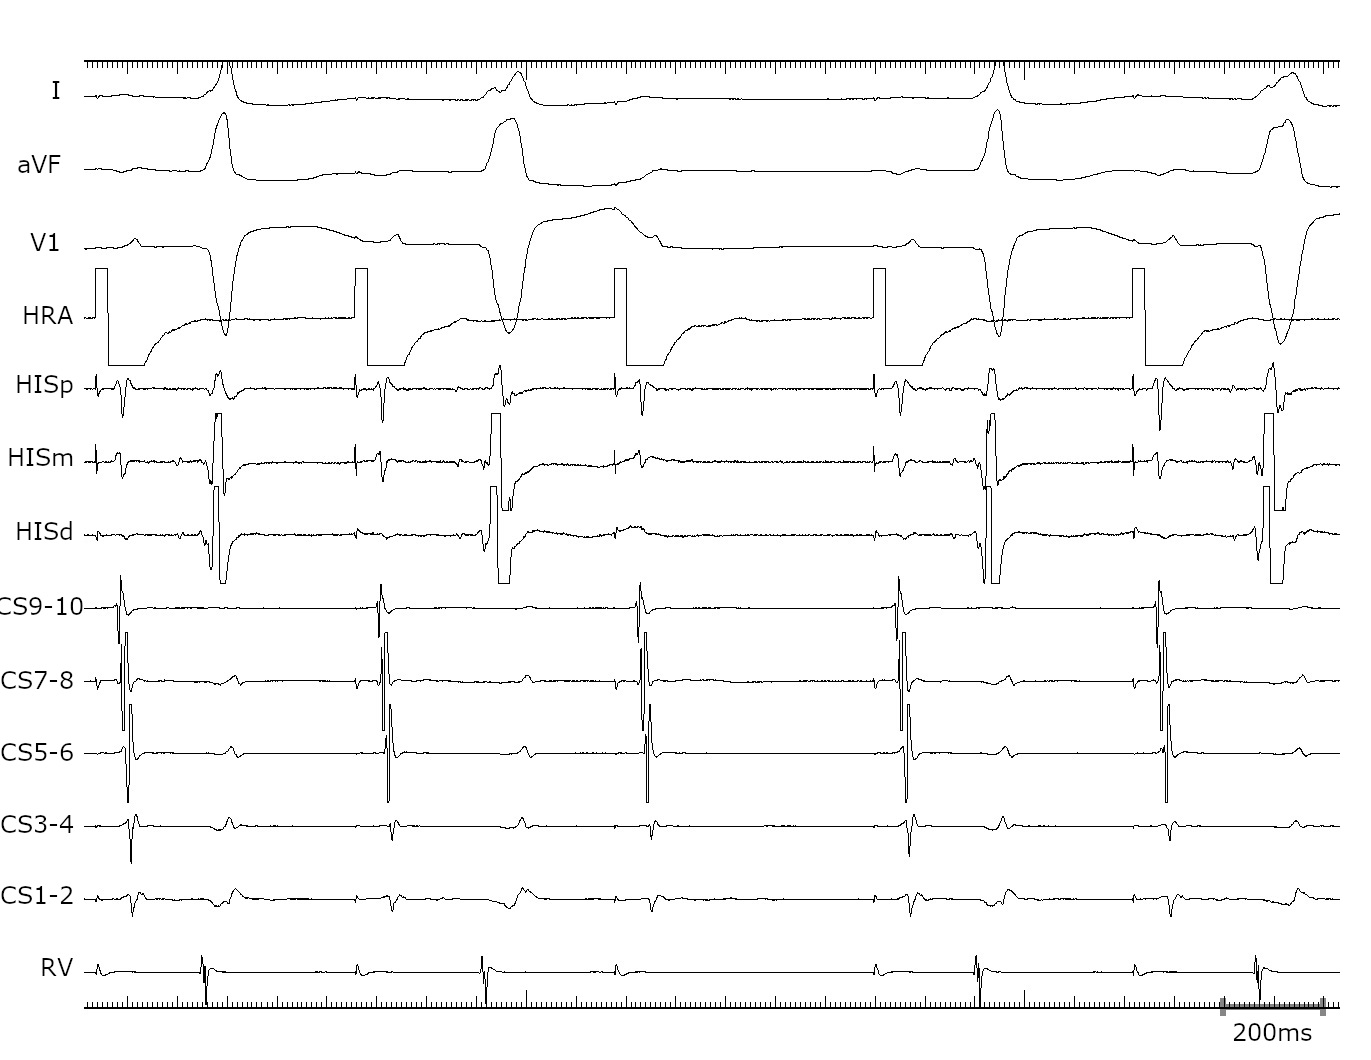

PVC on His

pvc.jpg

Diagnosis

• Concealed nodoventricular AP

• Orthodromic tachycardia

• Successful ablation at RIE